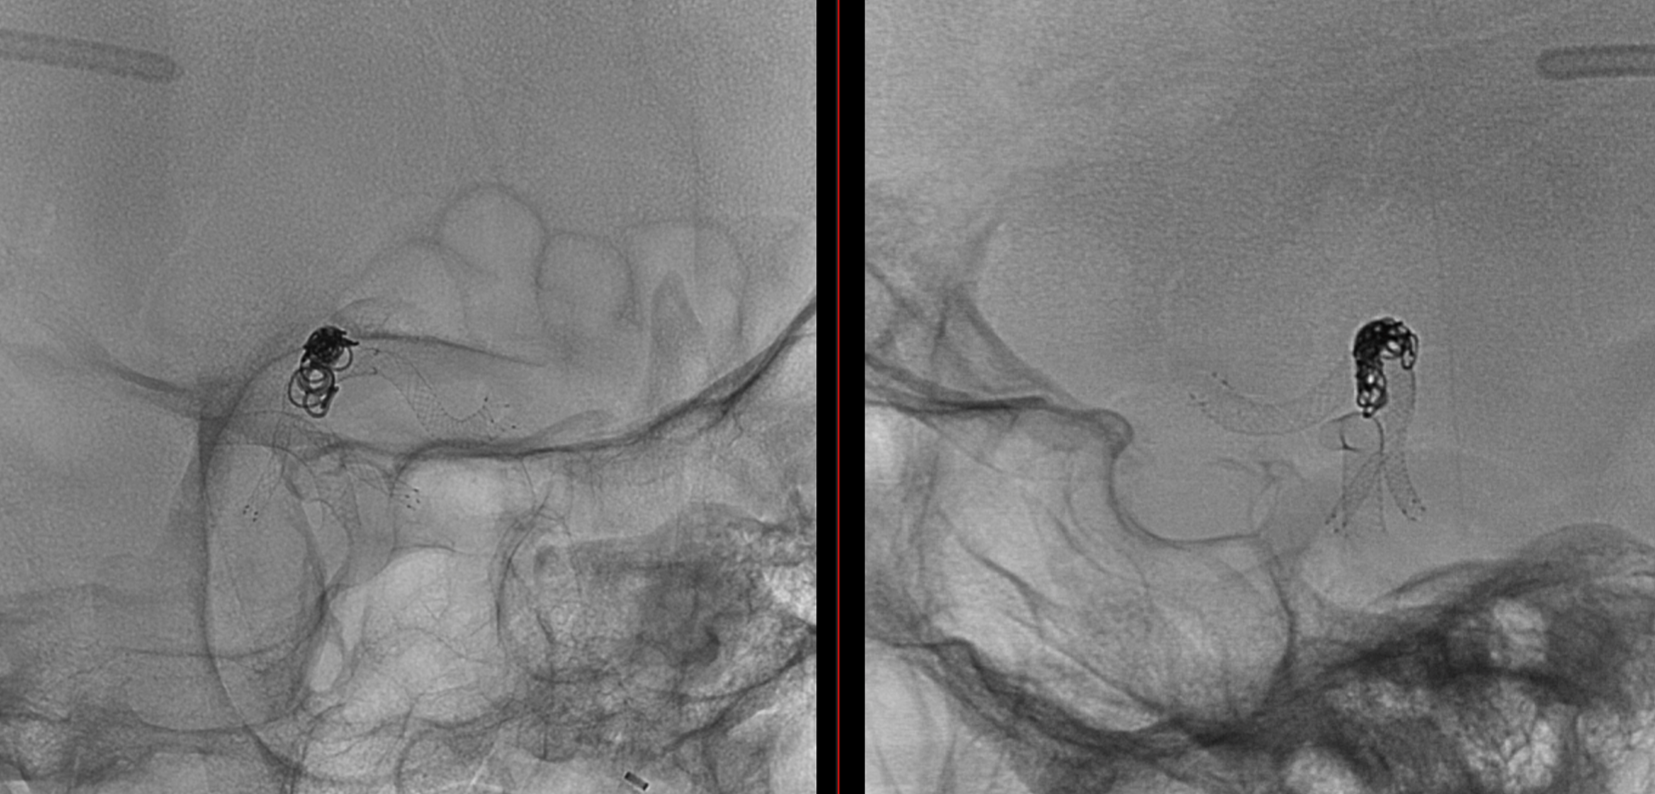

Noncontrast / dry Vaso-CT, 22 cm FOV 20 seconds acquisition, followed by a secondary reconstruction with 50% FOV and 5123 resolution; Thick MIP.

Two Lvis EVO have been used (in inverse Y or ? lambda shape). The first from the left PCom into the left SCA. The second from the left PCom into the right SCA. Another microcatheter in jailed in the aneurysm for the subsequent coiling.

There are no labels or arrows on any of the devices. If you are not sure what is going on, we suggest studying the images until you do.

Thick MIP reconstruction of a Vaso-CT acquired with manual injection of right vert and left ICA at the same time. Vaso-CT, 22 cm FOV 20 seconds acquisition, followed by a secondary reconstruction with 67% FOV and 5123 resolution; Thick MIP.

The procedure finished with coiling of the basilar tip around the stents and PTA of right SCA stent at the crossing of the other stent

Vas is das? You figure it out…

Post Rx. The key to this procedure, other than sophisticated understanding of the problem and the materials to be used, is a consistently effective antiplatelet state. Doing this without IIbIIIa in the lab for example risks major disaster.